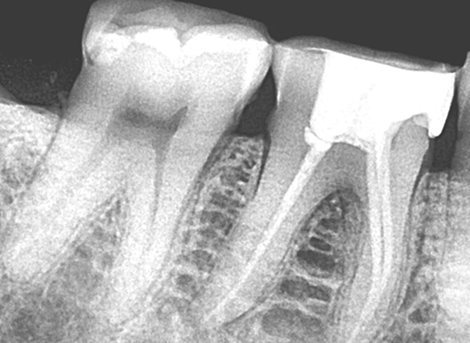

Diagnosis & X-Ray

Diagnosis & Preparation